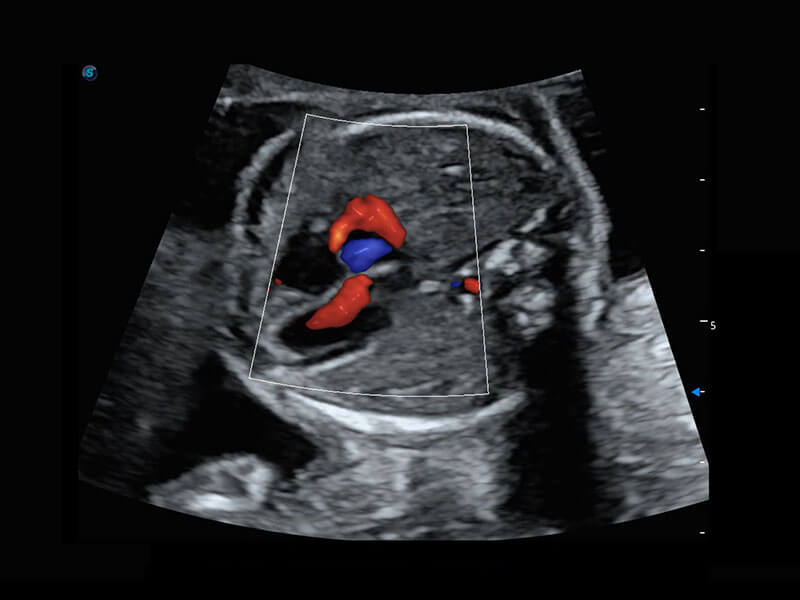

新生儿肝血管癌

新生儿脊髓圆锥

新生儿心脏

P60搭载宽频带线阵探头、宽景成像、弹性成像技术,为您提供乳腺应用方案。P60支持高频相控阵探头、线阵探头、腹部高频探头、腹部微凸探头等,丰富的探头群搭载敏感的彩色血流成像,适用于新生儿多种脏器检测要求,满足新生儿筛查需求。